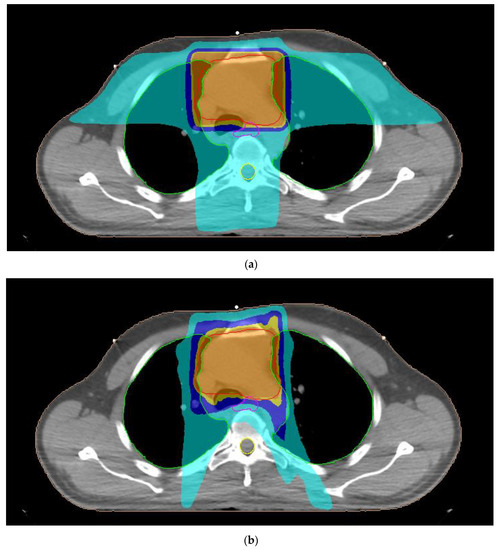

A typical dose distribution of a patient with thymoma from 3D-CRT, 7F-IMRT, 5F-IMRT, FA-VMAT and PA-VMAT plans is presented in Figure 1. The dose parameters for the PTV are summarized in Table 3. The mean TC, HI and CN for 3D-CRT were 58.4%, 1.11 and 0.48, respectively. The corresponding parameters for IMRT plans reached 95.6%, 1.06 and 0.83 whereas those for VMAT plans were up to 95.7%, 1.07 and 0.82.

Figure 1.

Typical dose distribution around the target volume, shown in red color, for (a) three-dimensional conformal radiotherapy, (b) seven-field intensity modulated radiation therapy, (c) five-field intensity modulated radiation therapy, (d) full-arc volumetric modulated arc therapy and (e) partial-arc volumetric modulated arc therapy techniques of a male patient with thymoma. The 95%, 90%, 75% and 45% isodoses are presented with orange, dark yellow, dark blue and light blue colors, respectively. The lungs, esophagus and spinal cord are denoted by the green, pink and yellow contours, respectively.